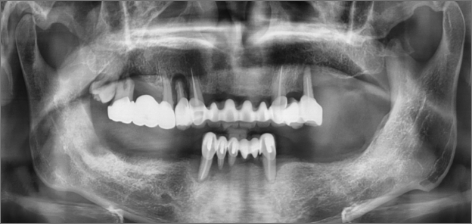

초진 : 2014.06.13

THE 이해승치과에서 2014년에 치료 받으신 40대 환자분의 사례입니다. 흡연과 음주가 근본 원인이 되어 2014년 전악 임플란트 치료를 받으셨습니다. 감사하게도 저희와 함께 꾸준히 8년간 관리를 동행하시며 추가적인 전신 질환 없이 건강한 50대를 보내고 계십니다. 치료 경험을 통해 변화를 만드신 환자분을 존경합니다.